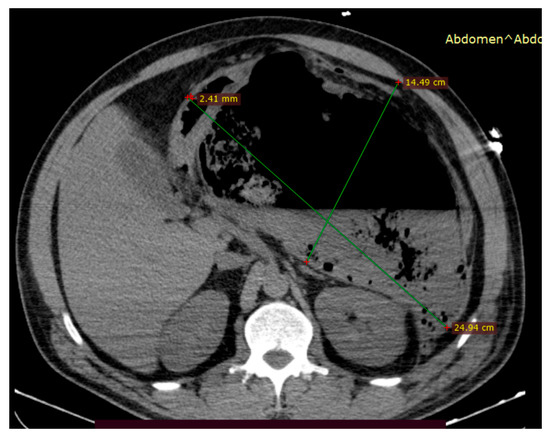

Clinical course: She was readmitted one year after the last evaluation (30 December 2024) in critical condition with severe abdominal pain for more than 72 h prior to admission. The patient described multiple prior episodes of severe abdominal pain over the last month, which were managed with over-the-counter paracetamol. Contrast-enhanced CT scan performed in the emergency department showed severe necrotizing pancreatitis with an mCTSI score of 10, involving a 25 × 15 cm compressive and partially encapsulated peripancreatic collection causing compartment syndrome, as shown in Figure 6, along with bilateral pleural effusions. The intra-abdominal pressure 8 h after admission was 290 mmH2O. Exploratory laparotomy was performed due to the lack of a fully matured wall and revealed pancreatic necrosis with peritonitis; lavage and drainage of the necrotic tissue were performed.

Figure 6.

An abdominal CT scan performed within 24 h of admission showed a large mixed-type partially encapsulated peripancreatic necrotic collection (approximately 50% necrosis) causing organ compression and severe abdominal compartment syndrome.